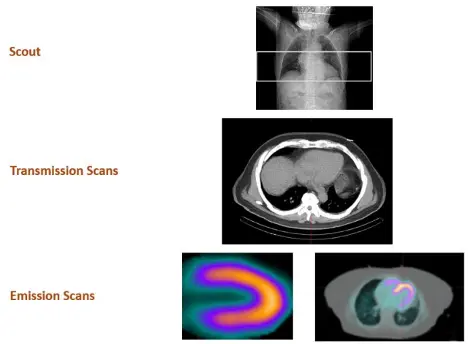

tl;dr: We collect transmission and perfusion images and superimpose them on one another. The CT and perfusion contours of the heart should be properly aligned (co-registration).

- Scout image to localize the heart

- Transmission scans – most commonly done with low-dose CT AC

- Emission scans

- Patient is